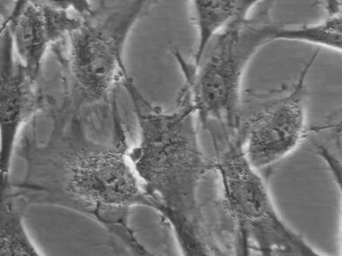

7. 细胞形态:成纤维细胞样或上皮细胞样

1. 形态特征:典型成纤维细胞样或上皮细胞样形态,贴壁培养生长。